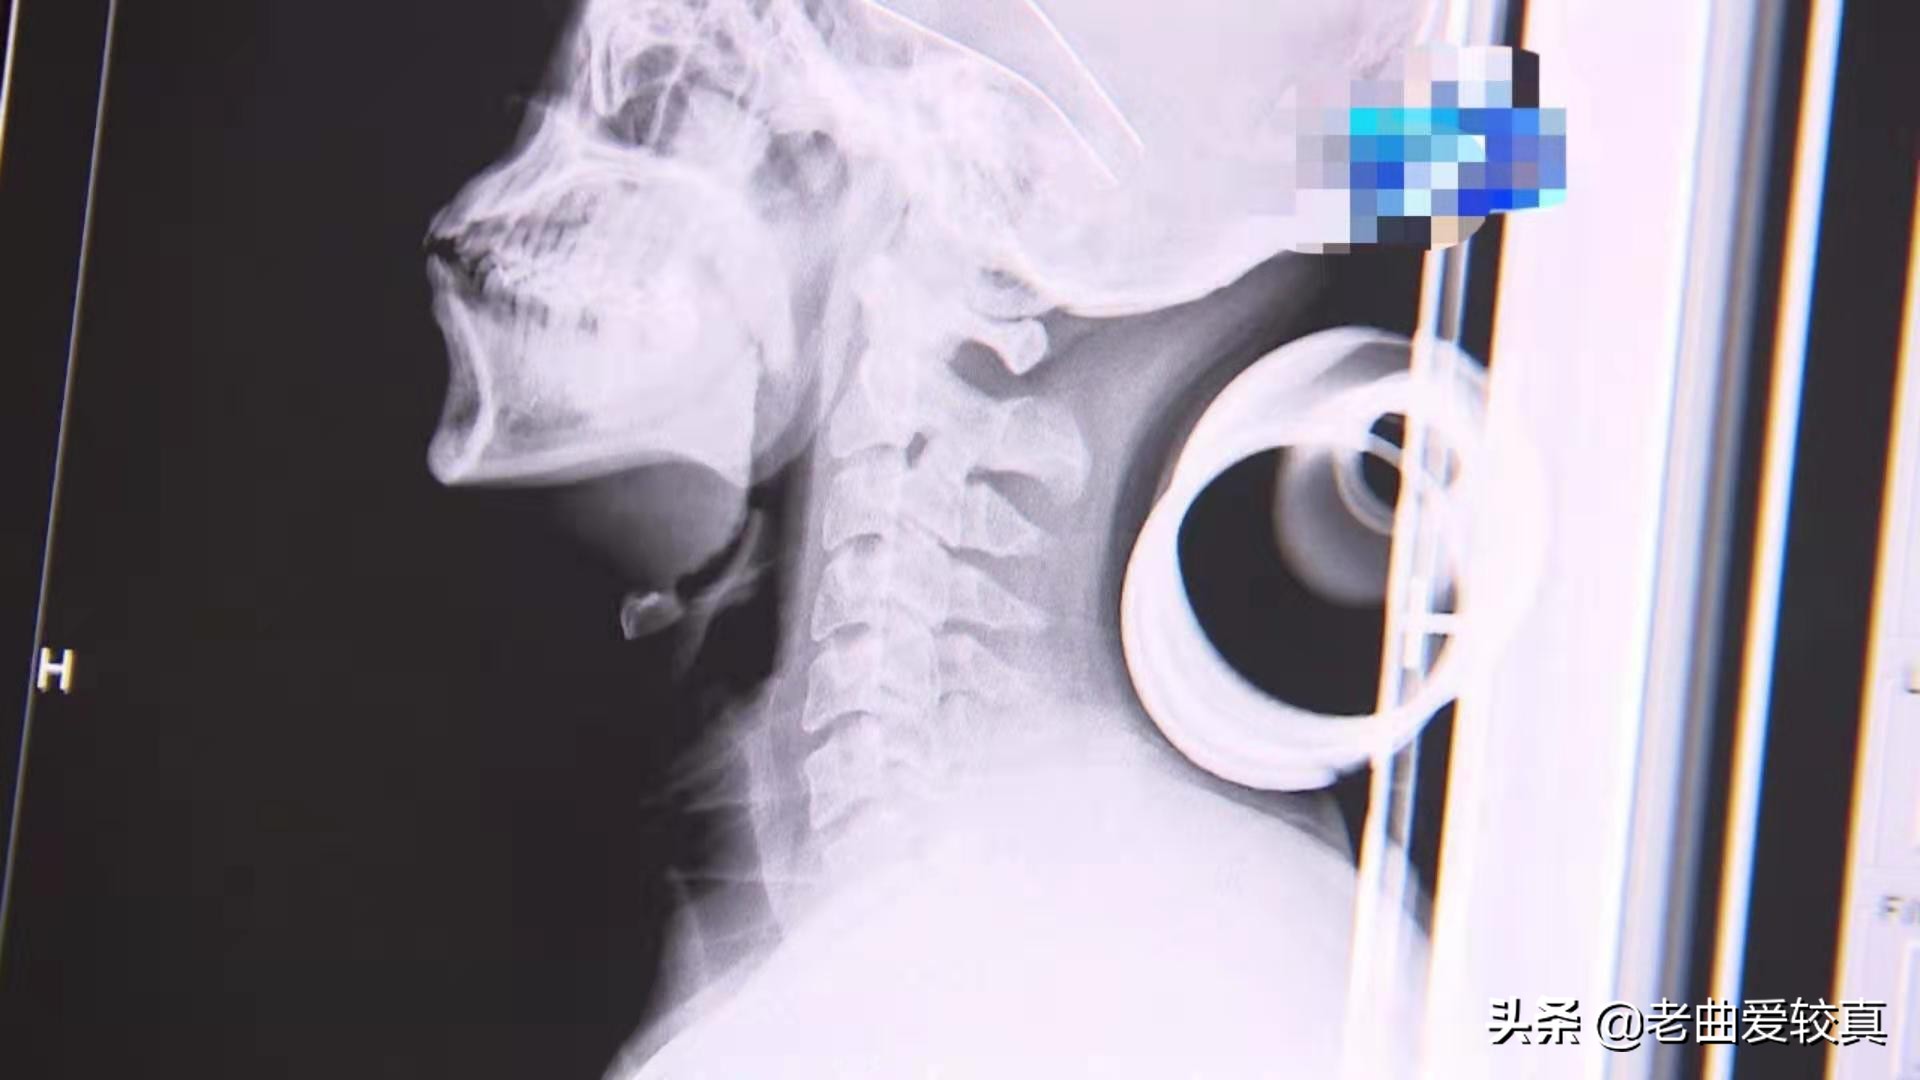

右面图是脖子底下枕着一个酒瓶子的X光片

大夫说我的颈椎还可以,骨质增生不明显,暂时没有颈椎病的迹象。

医生说从侧面看人的颈部似乎是直的,但是里头的颈椎是向前突的,从X光片显像来看:颈椎各个椎体后缘形成一个连续光滑的曲线。这叫颈椎的生理曲度。两张拍出来的X光片,枕不枕啤酒瓶子老曲颈部生理弯曲都是向前弯的,没有太大区别。